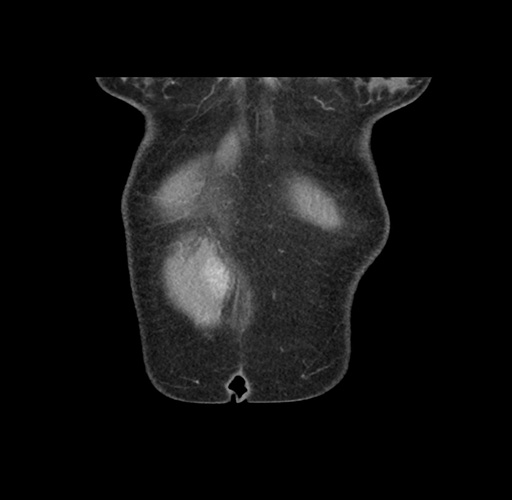

Imaging Analysis

Look through the patient's CT scan to identify any areas of concern for the necessary procedure.

Based on your CT findings, which issue(s) would give reason for "planned slowing down moment(s)" in this case?